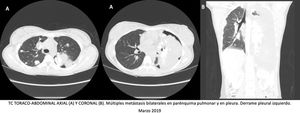

La radiografía y la tomografía computarizada de tórax mostraron múltiples masas pulmonares y pleurales bilaterales con calcio en su interior, derrame pleural izquierdo y una lesión blástica en cabeza humeral derecha (fig. 1). La anatomía patológica de la punción de una masa pulmonar confirmó el diagnóstico de metástasis de osteosarcoma.

Radiografía simple de tórax PA A) y tomografía computarizada toraco-abdominal corte coronal B) al diagnóstico, donde se objetiva derrame pleural izquierdo masivo, lesión blástica en cabeza humeral derecha, múltiples imágenes de densidad calcio en parénquima pulmonar bilateral y pleura. TC de tórax corte axial C1 y C2) tras drenaje de derrame pleural, donde destacan múltiples metástasis bilaterales en parénquima pulmonar y en pleura, así como neumotórax izquierdo. Radiografía simple de tórax PA y lateral D.1 y D.2) a los 10 meses desde el diagnóstico, donde se demuestra un aumento en número y tamaño de los nódulos y masas pulmonares y pleurales bilaterales, derrame pleural izquierdo y aumento de la lesión primaria en cabeza humeral derecho.